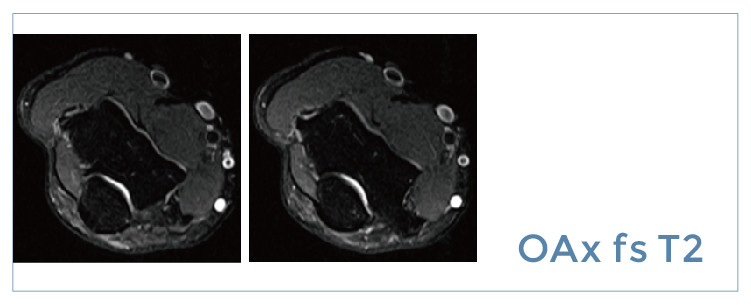

【朗润影像档案】磁共振影像病例分享(编号20190726)